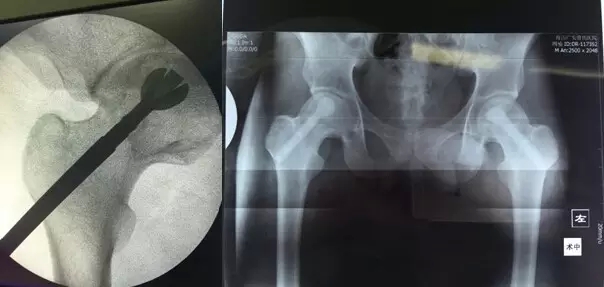

3月29日,舟山廣安醫(yī)院危立軍副院長為一名29歲的雙側(cè)股骨頭早期壞死患者成功實(shí)施了股骨頭壞死減壓、病灶清除、可注射人工骨植入術(shù)。這是當(dāng)前國際上在治療此類疾病的最先進(jìn)的微創(chuàng)手術(shù)技術(shù)。該項(xiàng)技術(shù)可以有效阻止股骨進(jìn)一步頭壞死而導(dǎo)致關(guān)節(jié)軟骨面塌陷,通過再造創(chuàng)面誘導(dǎo)骨再生、成骨而達(dá)到治愈目的。

治療股骨頭壞死的關(guān)鍵是終止病變進(jìn)展,在股骨頭壞死的早期階段,保留患者自身髖關(guān)節(jié)具有很高的臨床和社會(huì)價(jià)值。使之有可能往良性的軌道上發(fā)展。廣安醫(yī)院開展的“股骨頭壞死減壓、病灶清除、可注射人工骨植入術(shù)”,在保護(hù)已發(fā)生的壞死骨基礎(chǔ)上,同時(shí)通過生物學(xué)反應(yīng)促進(jìn)骨再生和病變組織修復(fù),有效恢復(fù)承重能力,防止股骨頭變形塌陷。該技術(shù)手術(shù)切口長約1-2厘米,創(chuàng)傷小,費(fèi)用低,恢復(fù)快,術(shù)后第二天即可出院,門診治療。